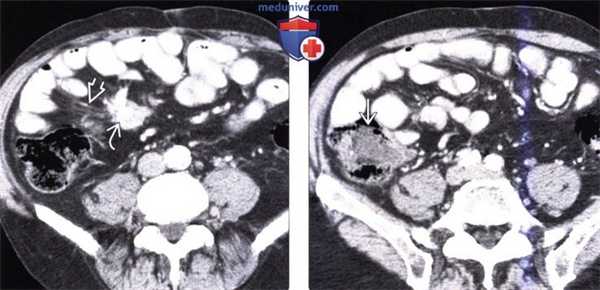

(Слева) На аксиальной КТ с контрастным усилением у мужчины 65 лет с жалобами на боль в животе визуализируется объемное образование в брыжейке с наличием кальцинатов в центре, видны также переполненные кровью брыжеечные сосуды. В правом нижнем квадранте также определяется стягивание брыжейки с деформацией кишечника.

(Справа) На КТ, полученной в венозную фазу контрастного усиления, визуализируется подозрительное объемное образование в илеоцекальной области, которое, как подтвердилось при хирургическом вмешательстве, является карциноидной опухолью. Обычно метастазы в брыжейке более очевидны на КТ по сравнению с первичной опухолью, особенно в венозную фазу контрастного усиления.